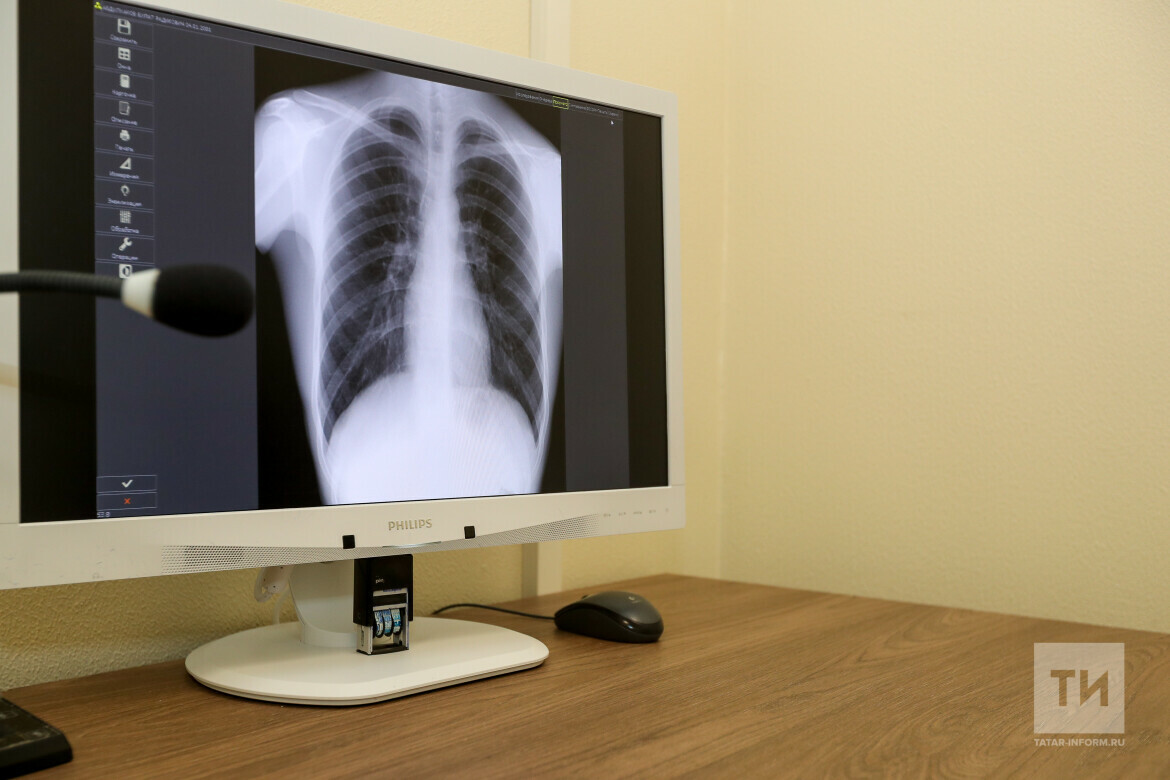

Врачи рассказали, как спастись от пневмонии

Идет неделя профилактики заболеваний органов дыхания, которая завершится 12 ноября Всемирным днем борьбы с пневмонией. «Татар-информу» в Республиканском центре общественного здоровья и медицинской профилактики рассказали о том, как защититься от этой болезни.

Фото: © Татар-информ